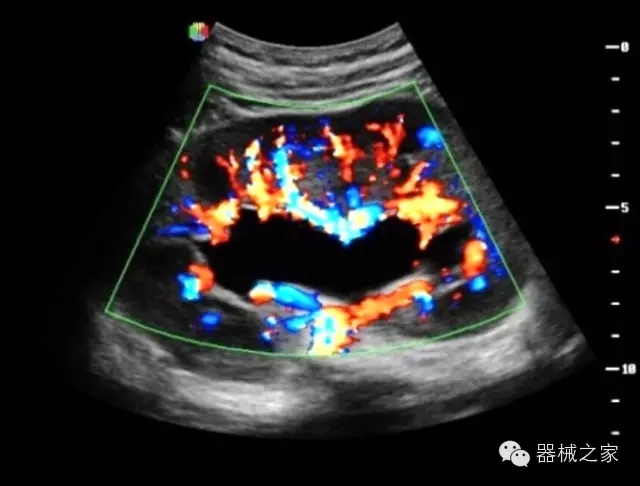

臨床圖片賞析

產(chǎn)品特點

·智能微血流成像技術(shù):智能微血流捕捉技術(shù)可以提取出隱藏在背景噪聲中的弱血流信號,大大提高低速血流的敏感性;

·高效3D/4D成像技術(shù):高速的4D幀頻,豐富的3D成像模式,智能斷層切片功能;